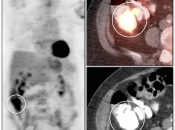

Value of Non-Attenuation Corrected (NAC) Images

Resolving Attenuation Correction Artifacts:

The CT images obtained during an exam are not only used for “anatomic” interpretation. They are also used for “attenuation correction” (AC) of the PET images, generating the much more useful AC PET images used for interpretation.

Unfortunately, attenuation correction of PET images can result in falsely elevated metabolic activity in regions of high CT density (e.g. metallic devices, oral contrast, calcification).

In such cases, these areas must be reviewed on the NAC (non-attenuation correction) images. If these regions are not also hypermetabolic on the NAC images, then their apparent increased FDG-uptake on the AC images is artefactual.

This phenomenon is almost exclusively seen with older PET/CT scanners, as most modern scanners utilize newer algorithms that do not “over-correct” in these areas of increased density.